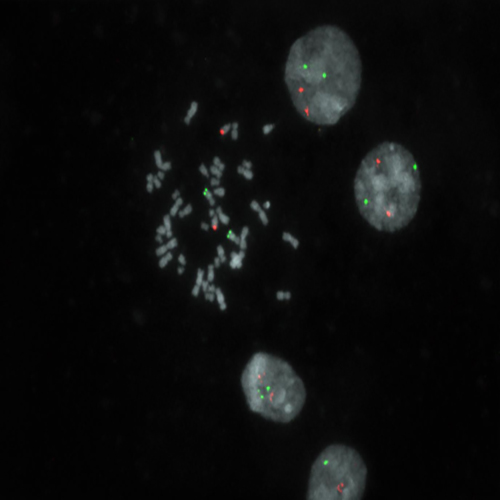

FGFR1 (8p11) Break probe hybridization to a tissue section showing a normal pattern.

FGFR1 has been implicated in the tumorigenesis of haematological malignancies, where it is frequently involved in balanced chromosomal translocations, including cases of chronic myeloid leukemia (BCR-FGFR1 fusion) and the 8p11 myeloproliferative syndrome/stem cell leukemia-lymphoma syndrome, which is characterized by myeloid hyperplasia and non-Hodgkin's lymphoma with chromosomal translocations fusing several genes, the most common being a fusion between ZNF198 and FGFR1. The FGFR1 (8p11) Break FISH probe is optimized to detect translocations involving the FGFR1 gene region at 8p11 in a dual-color assay on FFPE tissue sections.